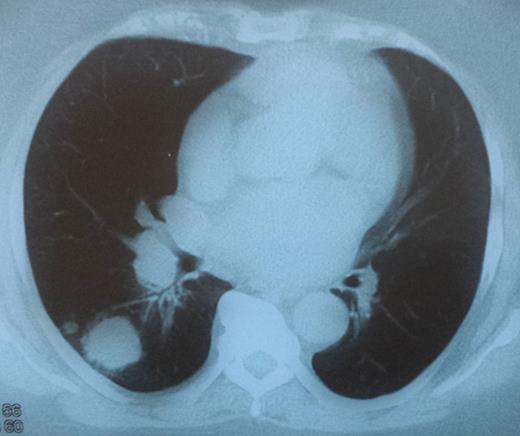

A CT scan showing a 6.2-cm mass pressuring and infiltrating the trachea and surrounding soft tissue.

Patient was submitted to adjuvant chemotherapy as well as radiation therapy. She underwent two cycles of chemotherapy with cisplatin 70 mg/kg once a week with concomitant radiotherapy, which was abruptly terminated because of toxicity. Patient died 5 months after the surgery due to airway compromise (direct infiltration of tumor to trachea causing airway obstruction).

Surgical excision of primary thyroid SCC with adjuvant radiotherapy and chemotherapy is the optimal treatment. However, many studies suggest that it is relatively radio-resistant and has poor response to chemotherapy [4, 8], leaving complete surgical excision the only chance of prolonging survival of these patients [9]. Patients with primary thyroid SCC have a very poor prognosis and the main cause of death is respiratory interference by direct invasion or compression of the trachea [10].